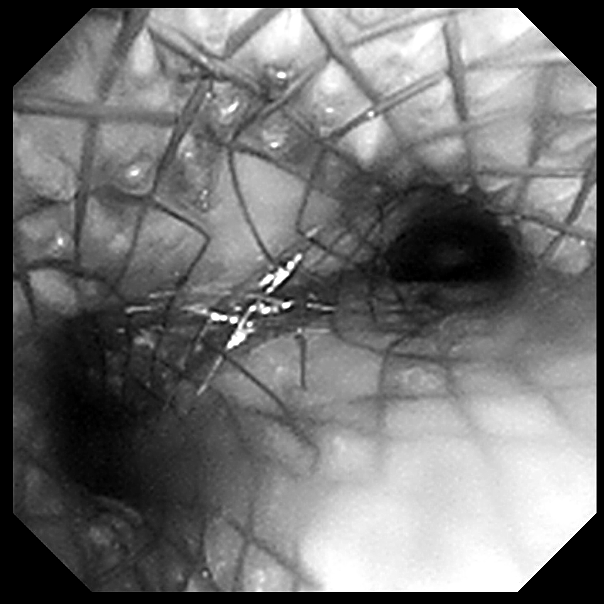

手术团队果断进行电圈套器套切肿瘤、止血治疗,经处理后管腔明显通畅,镜下见气道肿瘤浸润范围从气管下段一直到隆突,右主气管管腔中度狭窄,呼吸介入团队在导丝引导下成功置入 Y 型覆膜支架。术后患者呼吸困难症状明显改善,欣喜的同时也感受到了自由呼吸的来之不易。